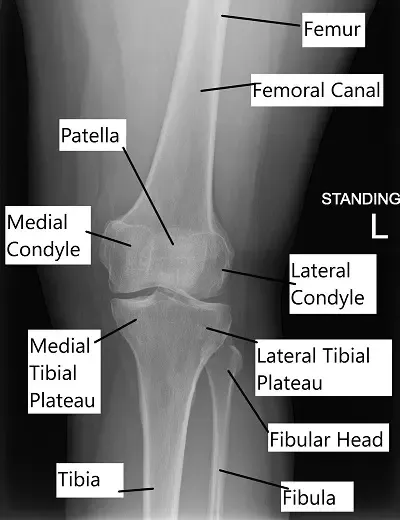

X-ray showing knee anatomy.